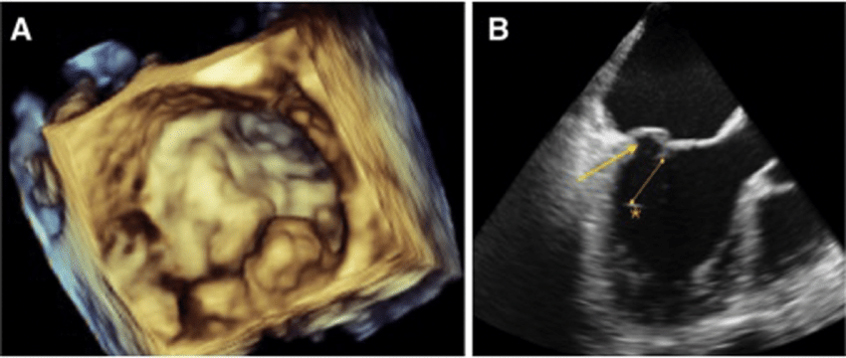

3. We have advanced echo tools such as 3D-Echo imaging and Strain imaging